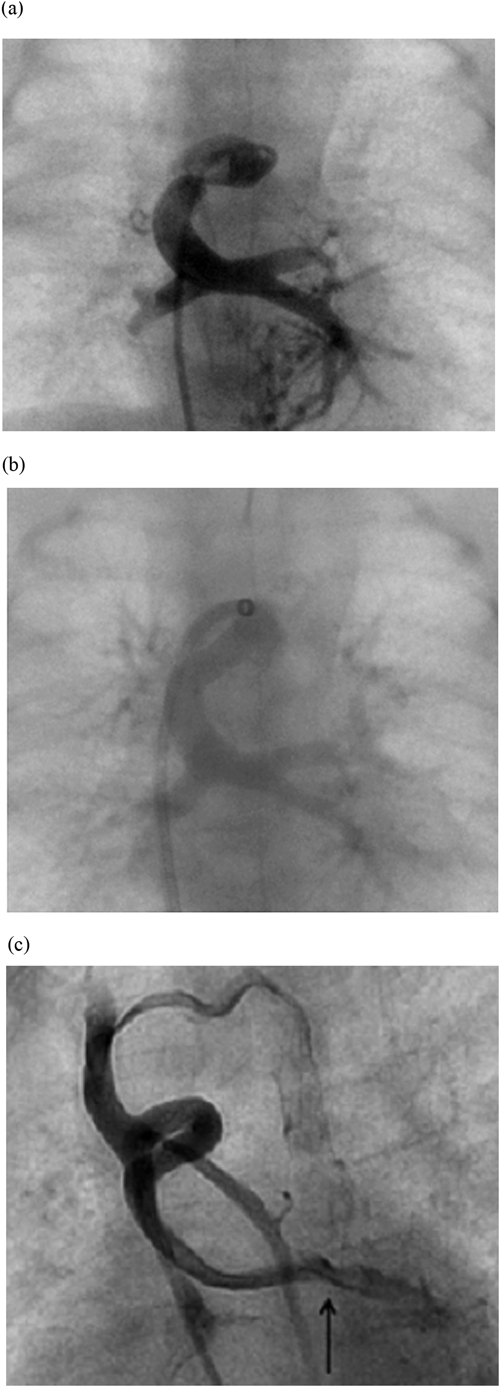

Three hours after birth, the patient was placed under general anesthesia. First, we introduced a 5-Fr short sheath into the right femoral vein. Using a 0.018-inch Radifocus guide wire and a 4-Fr Judkins coronary right catheter, we delivered a 2.3-Fr Progreat microcatheter to the common pulmonary venous chamber (CC). The mean CC pressure was 21 mmHg. An angiogram revealed severe stenosis of the VV (Fig. 2a). Next, we replaced the short sheath with a 5-Fr Cook long sheath and advanced it to the orifice of the VV draining into the right SVC. Using a 0.018-inch Radifocus guide wire, a 2.3-Fr Progreat microcatheter, and a 4-Fr Judkins coronary right catheter, we placed the distal side of the 5-Fr Cook long sheath across the stenosis. Using the 5-Fr Cook long sheath and a 0.014-inch Asahi Grand Slam wire, we implanted a DES (Resolute Integrity™ 4.0×9.0 mm) (Fig. 2b). The patient’s oxygen saturation consequently improved from 75% to 85% at a 0.21 fraction of inspired oxygen.

Fig. 2 Angiogram displaying anteroposterior views of the obstructed vertical vein (a) prior to and (b) after stent implantation. (c) Patent vertical vein 4 months after stent implantation. Contrast medium injected into the right superior vena cava flowed into the CC via the vertical vein (arrow).

At 33 days of age, we performed a diagnostic catheter examination. The pressure gradient across the stent was 0 mmHg. Patency of the stent was confirmed by an angiogram. The mean PA pressure was 26 mmHg, which exceeded the level at which the patient would have been a candidate for the Glenn procedure.

At 4 months of age, we performed another diagnostic catheter examination. The mean PA pressure was 15 mmHg. The pulmonary blood flow/systemic blood flow ratio and pulmonary resistance index were 2.3 and 2.3 units×m2, respectively. These values were suitable to proceed with planning for the Glenn procedure. An angiogram revealed that the stent remained widely patent (Fig. 2c). The diameter of the stent was 3.4 mm on the angiogram. Blood flow was detected from the SVC to the CC. The SVC pressure was 5 mmHg and the right atrial pressure was 3 mmHg, suggesting that the pressure gradient across the stent was 2 mmHg. At 5 months of age, we performed a bilateral bidirectional Glenn procedure and removed the stent. We discharged the patient 9 days following the procedure. Fig. 3 shows the specimen of the stent. The stented lumen was widely patent without stenosis or thrombosis. The configuration of the stent was fully circular. The neointimal thickness was approximately 500 µm. The minimum inner diameter of the stent was 3.8×1.9 mm. The stent strut was completely covered with the neointima. Chronic inflammatory cells, including lymphocytes, histiocytes, and neovessels, were observed around the struts.